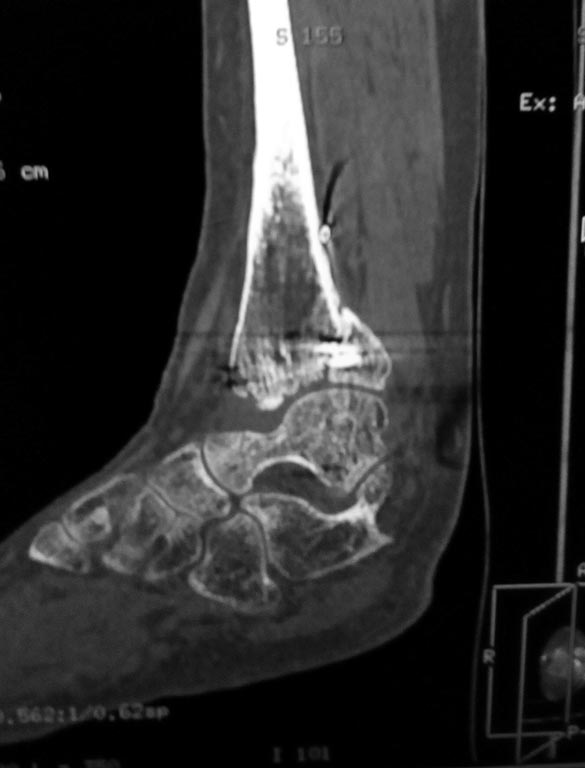

Мужчина, 1987 г.р. получил травму 10.2014. ДТП. Закрытый двухлодыжечный перелом костей костей левой голени, перелом заднего края большеберцовой кости с подвывихом стопы кзади, кнаружи.

Наложен дистрактор. Операция 10.2014: закрытая репозиция, остеосинтез спицами, винтами. В дальнейшем произошло ожидаемое усугубление нарушений взаимоотношений в голеностопном суставе.

Какой план лечения,на Ваш взгляд, предпочтительнее в данном случае? Возможно ли одномоментно устранить подвывих или только на аппарате Иллизарова? Первичные снимки после травмы отсутствуют. Критично ли "растоптана" латеральная суставная поверхность большеберцовой кости?

Мне кажется, что вопрос, поставленный Вами: "Возможно ли одномоментно устранить подвывих или только на аппарате Иллизарова?", отражает не совсем ясное понимание ситуации. Что значит устранить подвывих? А пластику ложных суставов внутренней лодыжки и заднего края большеберцовой кости не нужно делать? И ось голеностопного сустава нужно исправлять. То есть делать остеотомию наружной лодыжки (если она срослась, по снимку не очень понял). Артродез голеностопного сустава в такой ситуации очень сложен. Если же добиться сращения всех переломов в правильном положении, артродез вполне можно отсрочить на несколько лет, что для молодого пациента достаточно важно. Но в конечном счете все определяется Вашим умением и ясным представлением того, чего Вы хотите добиться своей операцией. Во вложении - в чем-то похожий случай. Оперировал эту пациентку 23 лет 11 лет назад через 8 месяцев после похожего на представленный Вами остеосинтез. На первой операции перелом малоберцовой кости в нижней трети был просто не замечен. За счет восстановления оси быстро развившийся артроз протекал благоприятно. В результате артродез был выполнен только в прошлом году, через 10 лет после второй операции. И боли беспокоили пациентку только в течение года перед артродезом.